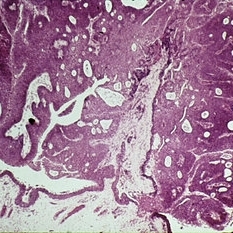

Slide 7-10

Feb 25 2019 by Lancaster Course in Ophthalmology

Conjunctival granulomas in a case of sarcoidosis.

Condition/keywords: granuloma, sarcoidosis